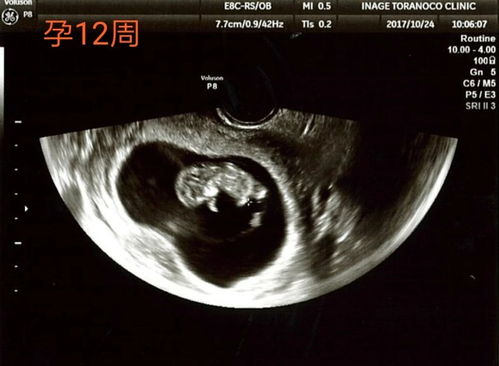

怀孕期间,孕妇们会经历多次B超检查,以确保胎儿的健康发育。其中,25周的系统B超检查尤为重要,它不仅能够全面了解胎儿的生长发育情况,还能对孕妇的养生保健提供指导。本文将详细介绍25周系统B超的检查内容、注意事项以及相关数据解读。

在25周左右,胎儿的身体各项发育已经基本完成,身长约为30厘米,重量可达750克。此时,胎儿的味觉和视力也趋于完善。系统B超可以观察胎儿的体型、身长、体重等指标,确保其正常发育。

系统B超可以观察胎儿的心肺功能和内脏发育情况,如心脏、肝脏、肾脏等。此外,还可以观察胎儿面部器官的发育,以及是否存在心血管畸形等问题。

羊水是胎儿在母体内的保护层,对胎儿的生长发育至关重要。系统B超可以监测羊水的深度和羊水指数,确保羊水量的正常。

脐带绕颈是孕期常见的并发症,系统B超可以观察脐带是否绕颈,以及绕颈的松紧程度,为临床治疗提供依据。